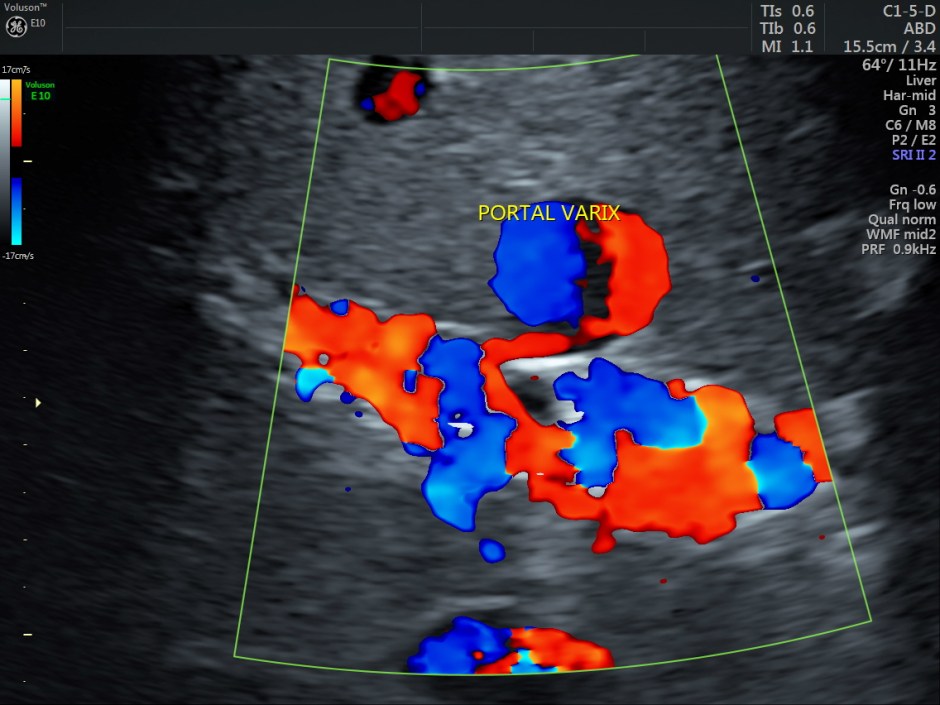

A prominent globular vascular structure of size 1.71 + 1.28 cms was seen in the right lobe.

The red globular structure seen in colour flow was striking.

A small feeding vessel leading from the portal vein entering the vascular structure is seen.